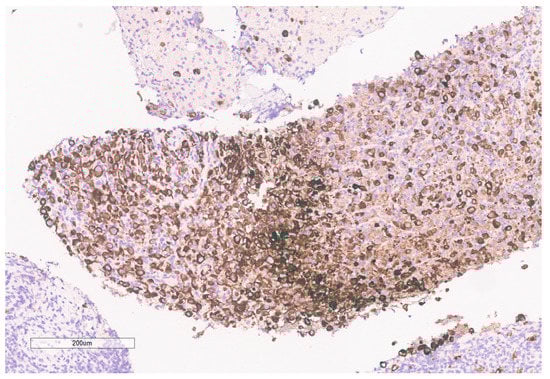

The biopsy of right kidney demonstrated mostly fibrinous material with small fragments of renal parenchyma with interstitial chronic inflammation and no definite tumor. The biopsy of a retroperitoneal lymph node showed high grade tumor composed of discohesive rhabdoid cells with highly atypical nuclei and eosinophilic cytoplasm involving lymphoid tissue with areas of necrosis and neutrophilic inflammation with necrosis and limited viable tumor cells (Figure 7). By immunohistochemistry, the cells were positive for pankeratin (Figure 8) and PAX8 (Figure 9) and negative for CK7, CK20, GATA3, CDX2, TTF1, CAIX, ERG, S100, CD34, CD30, SMA, desmin, OCT3/4 and CD163. The tumor cells showed diffuse loss of SMARCB1/INI-1 (Figure 10). The INI-1 was reviewed by several experienced pathologists that interpreted the stain as negative. While there is some background cytoplasmic and nuclear staining in the entire specimen, the norm is to compare staining with the adjacent internal positive control. Given that, in this case, the lymphocytes stained strongly positive for INI-1, it was appropriate to interpret this is as a negative stain in this context. As evidenced by the high-power image, the staining appears to be of a background variety and limited to the cytoplasm, in which the nuclei remain negative. Hence, this is interpreted as a negative stain.

Figure 10. INI-1 (BAF47) is negative in the tumor. Lymphocytes serve as an internal positive control.